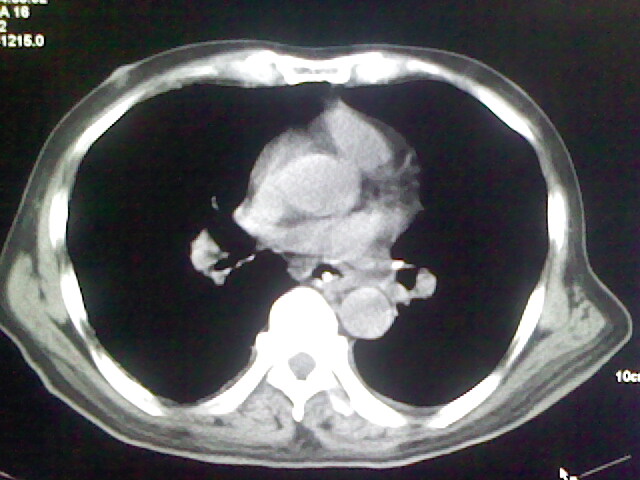

男,70岁,脑出血,长期卧床,左侧背部可触及肿块

慢性间质性炎症,与老年患者长期卧床相关,胸壁软组织及肋骨未见异常。

考虑右肺及左肺下叶炎症。

右肺及左肺下叶炎症。

考虑右肺及左肺下叶慢性炎症。

右侧肺部见片状密度增高影,边缘模糊。考虑炎症。另食管壁增厚。